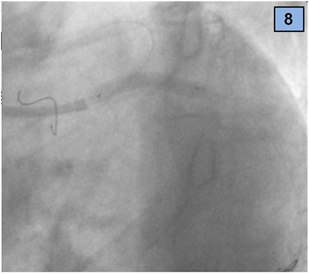

1. In order to treat the distal LMCA lesion, a CULOTTE STENTING technique was used:

2. A 3.5 x 30 mm zotarolimus drug eluting stent (DES) was implanted between the LM artery and CX, overlapped to the previous stent (CX, Figure 8).

Figure 8 DES implantation between the LM artery and CX, overlapped with the previous one.